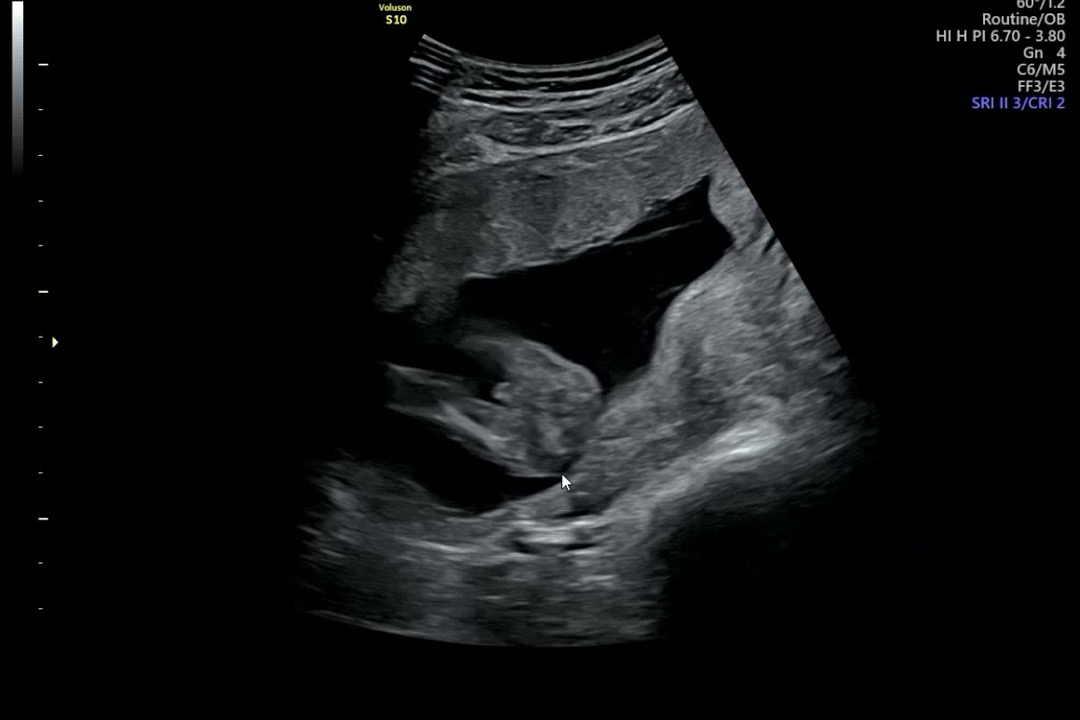

15주 아들일까요?

15주0일인데 확신의 아들일까요~?

넵, 🌶 입니다!

네 아들같아요~^^